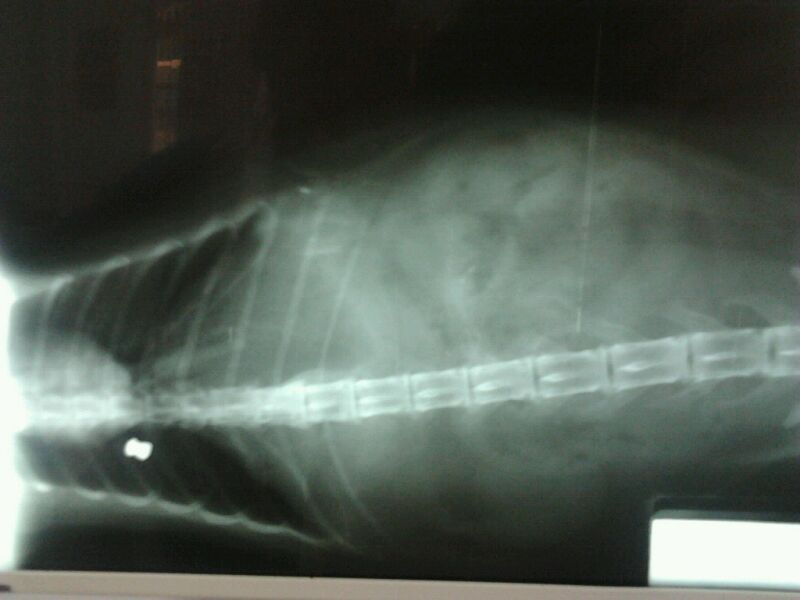

Ahora os adjuntaré las radiografías, para que veáis el balín.

Incluso ha puesto radiografías del balin. Por la penetración en el gato parece una arma potente, además no hay deformación ¿ no ?

Por lo que veo en la foto, su penetración oblicua, el angulo, la deformación o ensanchamiento que se ve en la segunda y sobre todo por el resultado de muerte en el pobre gato me atrevería a asegurar que ha sido producido por una carabina.

La deformacion del balin no es mucha.